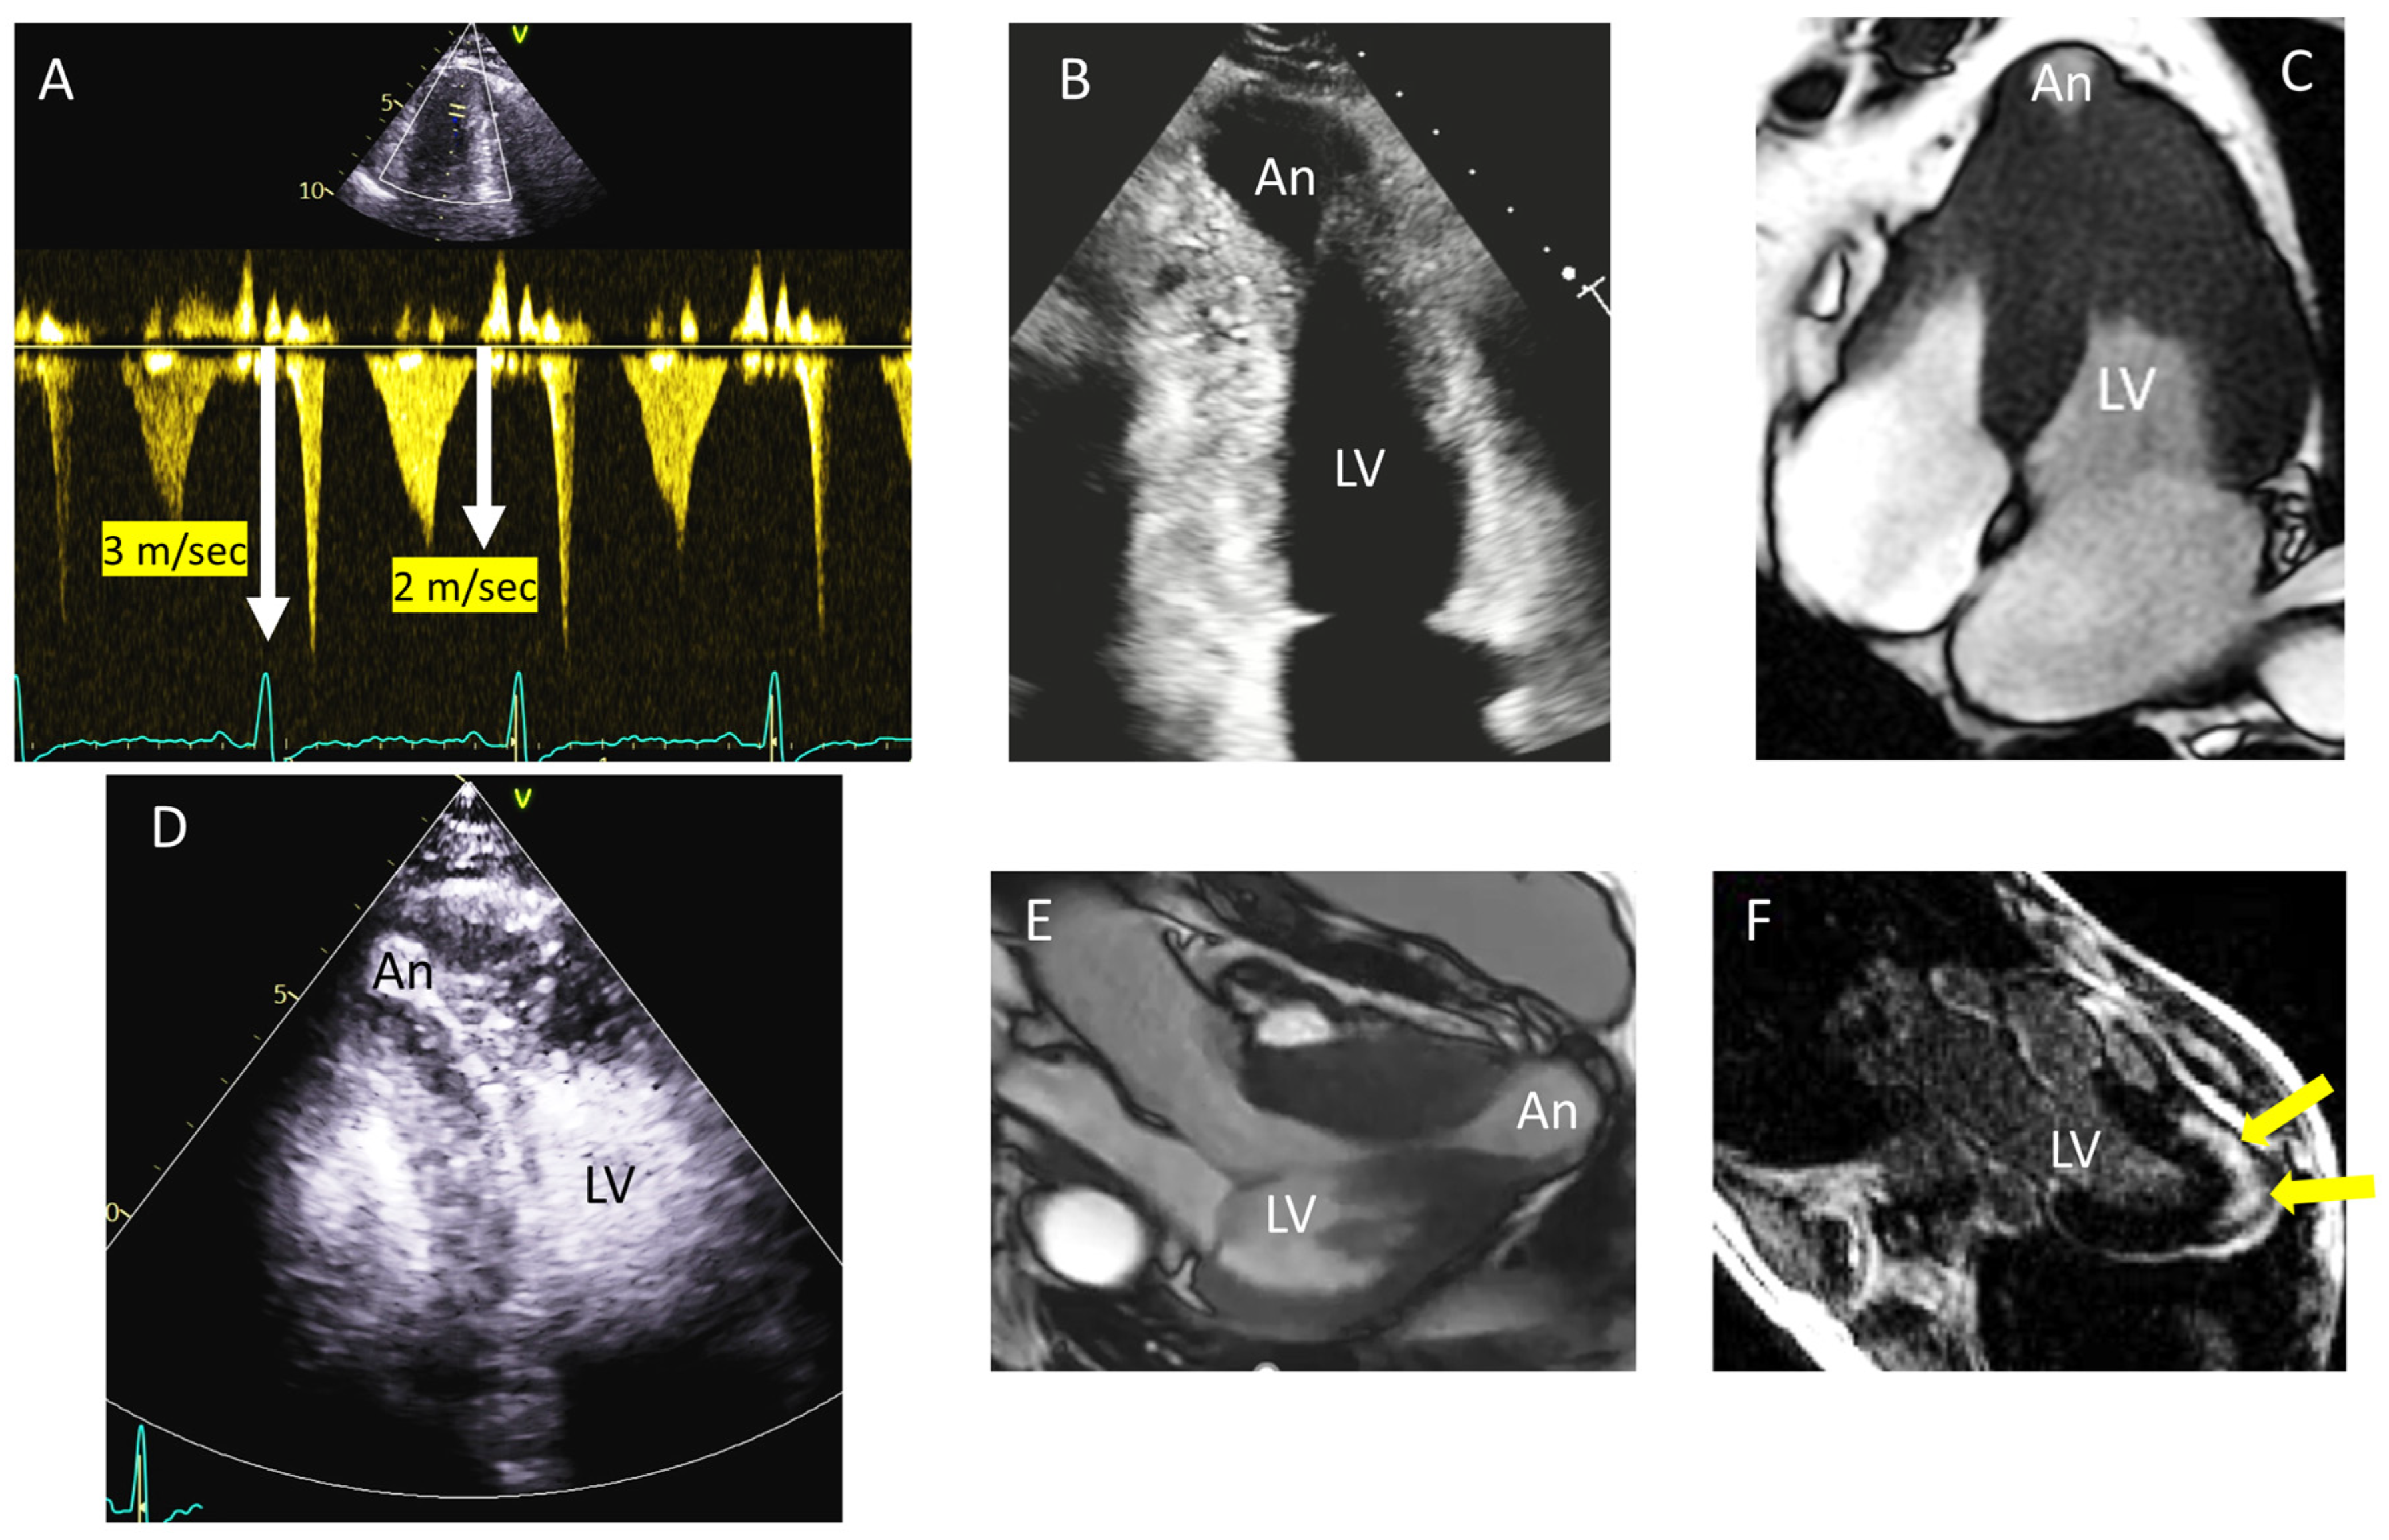

2. Distribution of Segmental Hypertrophy

3. Apical Hypertrophy (With or Without Aneurysm)

- Lo Russo, G.V.; Pepi, M.; Mushtaq, S.; Mantegazza, V.; Celeste, F. Is There a Typical Doppler Pattern in Patients With Apical Hypertrophic Cardiomyopathy With Aneurysm? JACC Case Rep. 2023, 14, 101836. [Google Scholar] [CrossRef]